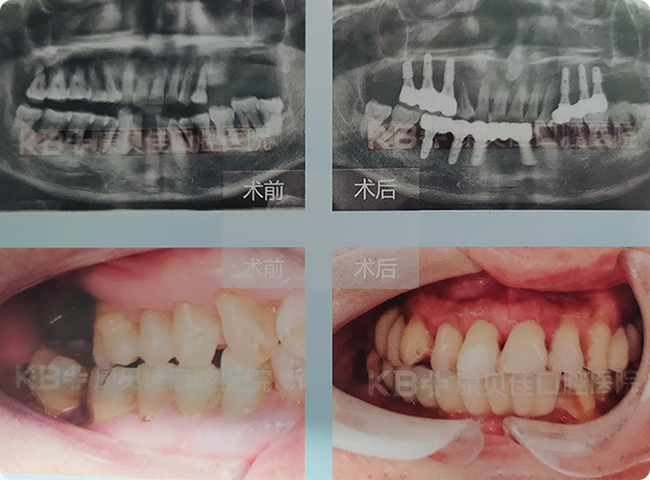

汪先生 58岁

因为年轻时没有做好口腔保健工作,40多岁时牙齿开始脱落。由于缺牙时间比较长,存在牙槽骨骨量不足的问题。康贝佳口腔种植专家决定帮他进行上颌窦内提升的同时植入种植体,缩短治疗周期。戴牙后什么都能吃,特别开心。

治疗方案:

上颌种植6颗 下颌种植4颗恢复7颗